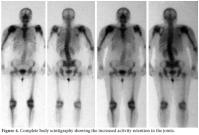

In the scintigraphic examination, we found increased activity involvement in both shoulders, especially in the right shoulder as well as on the right humeral head and in the distal phalanx of the finger. Both the scintigraphic and the radiological findings were compatible with secondary degenerative changes, especially in the benign bone pathologies (Figure 4). Furthermore, craniocervical magnetic resonance imaging (MRI) (especially FLAIR sequence) found cerebellar tonsillar herniation compatible with the Chiari type I malformation in the accompanying syrinx cavity in the cervical spinal cord (Figure 5). In addition, the arterial/venous Doppler ultrasonography (USG) results for both the lower and upper extremities were normal.